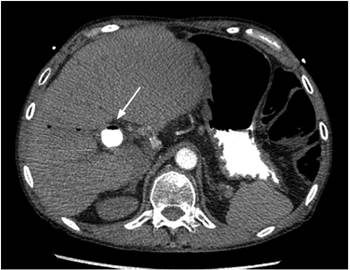

Se tomó una ecografía FAST que descartó taponamiento cardíaco, pero evidenció múltiples burbujas de aire en la vena cava; se trasladó inmediatamente a angiografía por TAC (bajo sospecha de embolia aérea), que mostró aire en la vena cava intrahepática (Figura 2) y émbolo aéreo en una de las arterias pulmonares subsegmentarias del segmento apical del lóbulo inferior derecho (Figura 3). Se trasladó a la paciente a la unidad de cuidados intensivos (UCI), se tomó ecocardiograma transtorácico que mostró colapso de la cava inferior, hallazgo esperado en un estado posreanimación, sin disfunción ventricular izquierda. La paciente evolucionó hacia la mejoría, se extubó al segundo día y se dio de alta a los 4 días sin complicaciones adicionales ni secuelas.

En el caso presentado se realizó una ecografía FAST que demostró aire en la vena cava, lo que, junto con el cuadro clínico, sugirió el diagnóstico de una embolia aérea, que fue confirmada con una angiografía por TAC realizada inmediatamente después de la fase inicial de la reanimación cardiorrespiratoria.